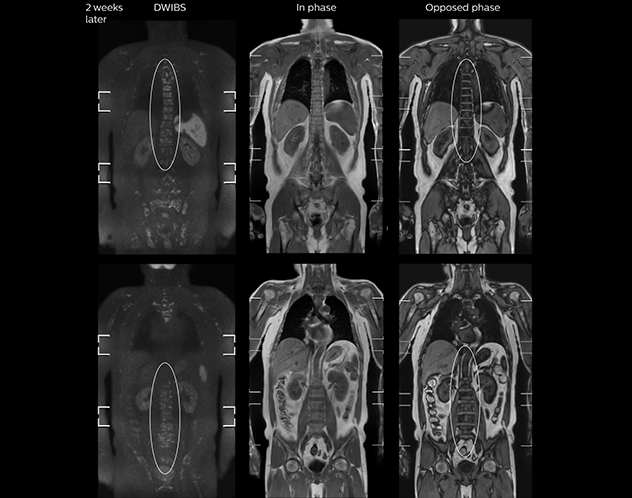

“When we limited the scan coverage to the area from neck to femur, we could fit more clinical information in approximately the same scan time. So, we added coronal mDIXON, sagittal T1-weighted, and sagittal STIR sequences to our examination, instead of performing only axial DWIBS and coronal single-shot TSE scans.”

The single shot T2-weighted TSE images are used for morphology and compared to DWIBS images to identify T2 shine-through. Sagittal STIR images are used in patients with inflammation or bone metastasis.

Kawasaki Sawai Hospital’s whole body protocol also includes an mDIXON FFE sequence. Because mDIXON provides images for four contrast types – water only, fat only, in-phase and out-of-phase – from a single acquisition, it is useful in many ways.

“mDIXON FFE allows us to quickly get information we need to assess the presence of fat. That gives us more information when we need to diagnose bone lesions, and when we are asked to judge fat-containing lesions such as hepatocellular or renal carcinoma,” Dr. Nobusawa says.

“The mDIXON fat images can help us to differentiate fatty bone marrow from bone lesions. This is especially useful in elderly people, who tend to have fattier bone marrow. The water images provide a high signal-to-noise ratio in the intestinal canal, which is valuable for visualizing lesions in the colon,” he says.

“In-phase and out-phase sagittal T1-weighted FFE images help us to visualize and further characterize bone lesions such as metastasis and bone-marrow hyperplasia that have high signal on DWI. These images are also used throughout radiotherapy, to monitor changes in the fatty bone marrow.”